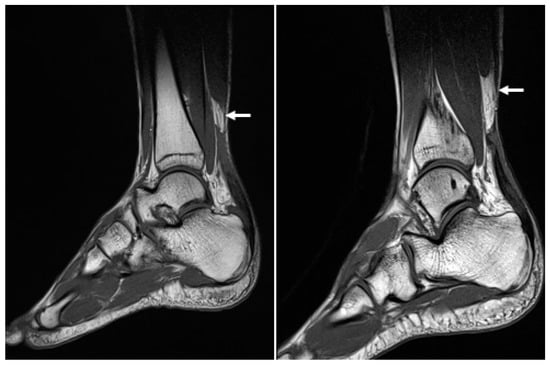

At the time of admission, the Thompson squeeze test was positive in both ankles, and digital exploration revealed dimpling 6 cm superior to the calcaneal tendon attachment site. Preoperative ankle radiographs showed no abnormality in the bone or surrounding soft tissue, other than the loss of Kager’s triangle (Figure 2). MRI confirmed the diagnosis of bilateral AT rupture (Figure 3).

Figure 2. Lateral conventional radiographs of both ankles following bilateral Achilles tendon rupture show marked thickening of the Achilles tendons, loss of the normal sharp anterior borders (white arrows), and effacement of the pre-Achilles/Kager’s fat pad.